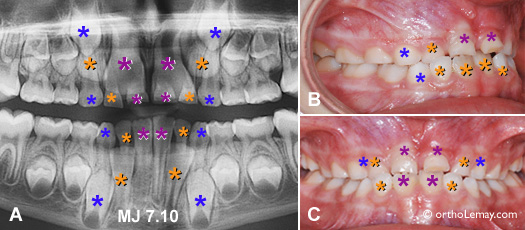

Cas MJ-VT

Cas MJ : (A) Problèmes d’éruption dentaire anticipés sur une radiographie panoramique montrant la différence de grosseur entre les dents de lait et les dents définitives. Les centrales supérieures permanentes prennent l’espace des centrales et des latérales temporaires! La différence est moins marquée à l’arcade inférieure mais les incisives permanentes sont beaucoup plus larges que les temporaires. (B, C) Apparence clinique; il est difficile de suspecter l’important manque d’espace qui affectera la région antérieure sans avoir recours à une radiographie.